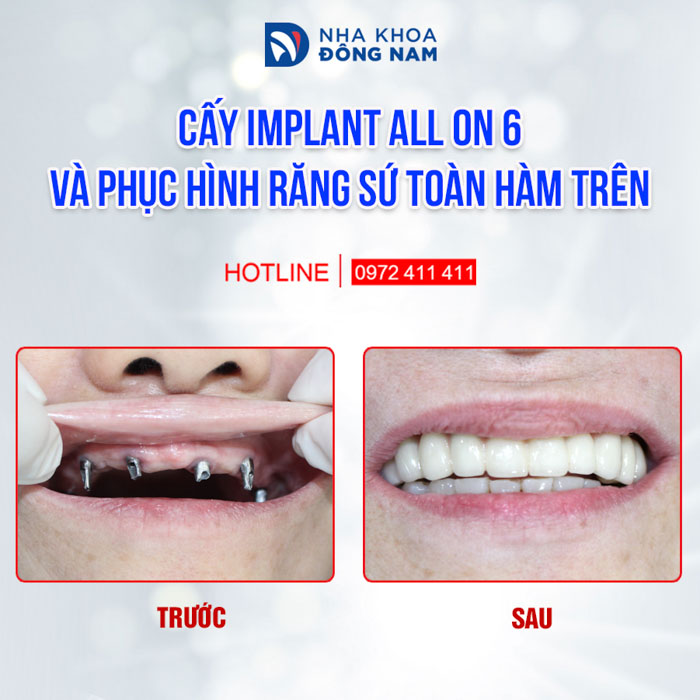

- Chứng nhận “Dịch Vụ Hoàn Hảo” dành cho dịch vụ Cấy Ghép Implant và Phục Hình Răng Sứ do chính khách hàng bình chọn.